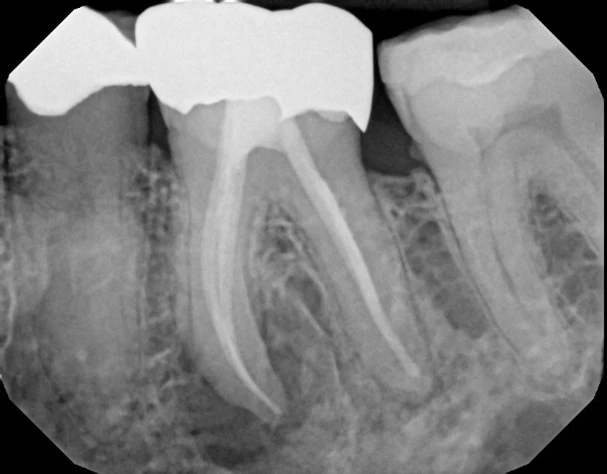

This patient saw a root canal specialist and was told the tooth needed extraction because the root canal did not work. The patient found Dr. Miner, and Dr. Miner did an apicoectomy and saved his tooth.